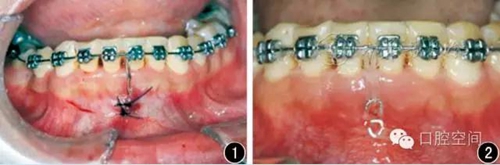

1.矯治設(shè)計和治療過程

20例成人深覆頜患者均接受了直絲弓矯治器治療(ROTH數(shù)據(jù),杭州新亞醫(yī)療器械公司),設(shè)計微螺釘支抗閉合式牽引壓低下前牙,改善深覆頜。下頜前牙經(jīng)過排齊階段,更換至0.018英寸(1英寸=25.4 mm)鎳鈦絲。在下頜中切牙之間前庭溝處,局麻下切開黏膜,下頜骨正中聯(lián)合部位植入一顆微螺釘(1.6 mm×9 mm,慈北醫(yī)療器械有限公司)。以直徑0.30 mm結(jié)扎絲連接微螺釘頭部,并穿出黏膜形成牽引鉤形狀(圖1)??p合黏膜切口后,微螺釘結(jié)扎絲牽引鉤和下前牙弓絲之間以鏈狀皮圈加力,進行下前牙壓低治療(圖2)。深覆頜矯治后,局麻下去除微螺釘植體。

圖1下頜骨正中聯(lián)合部位植入微螺釘示意圖

圖2應(yīng)用微螺釘閉合牽引壓低下前牙示意圖